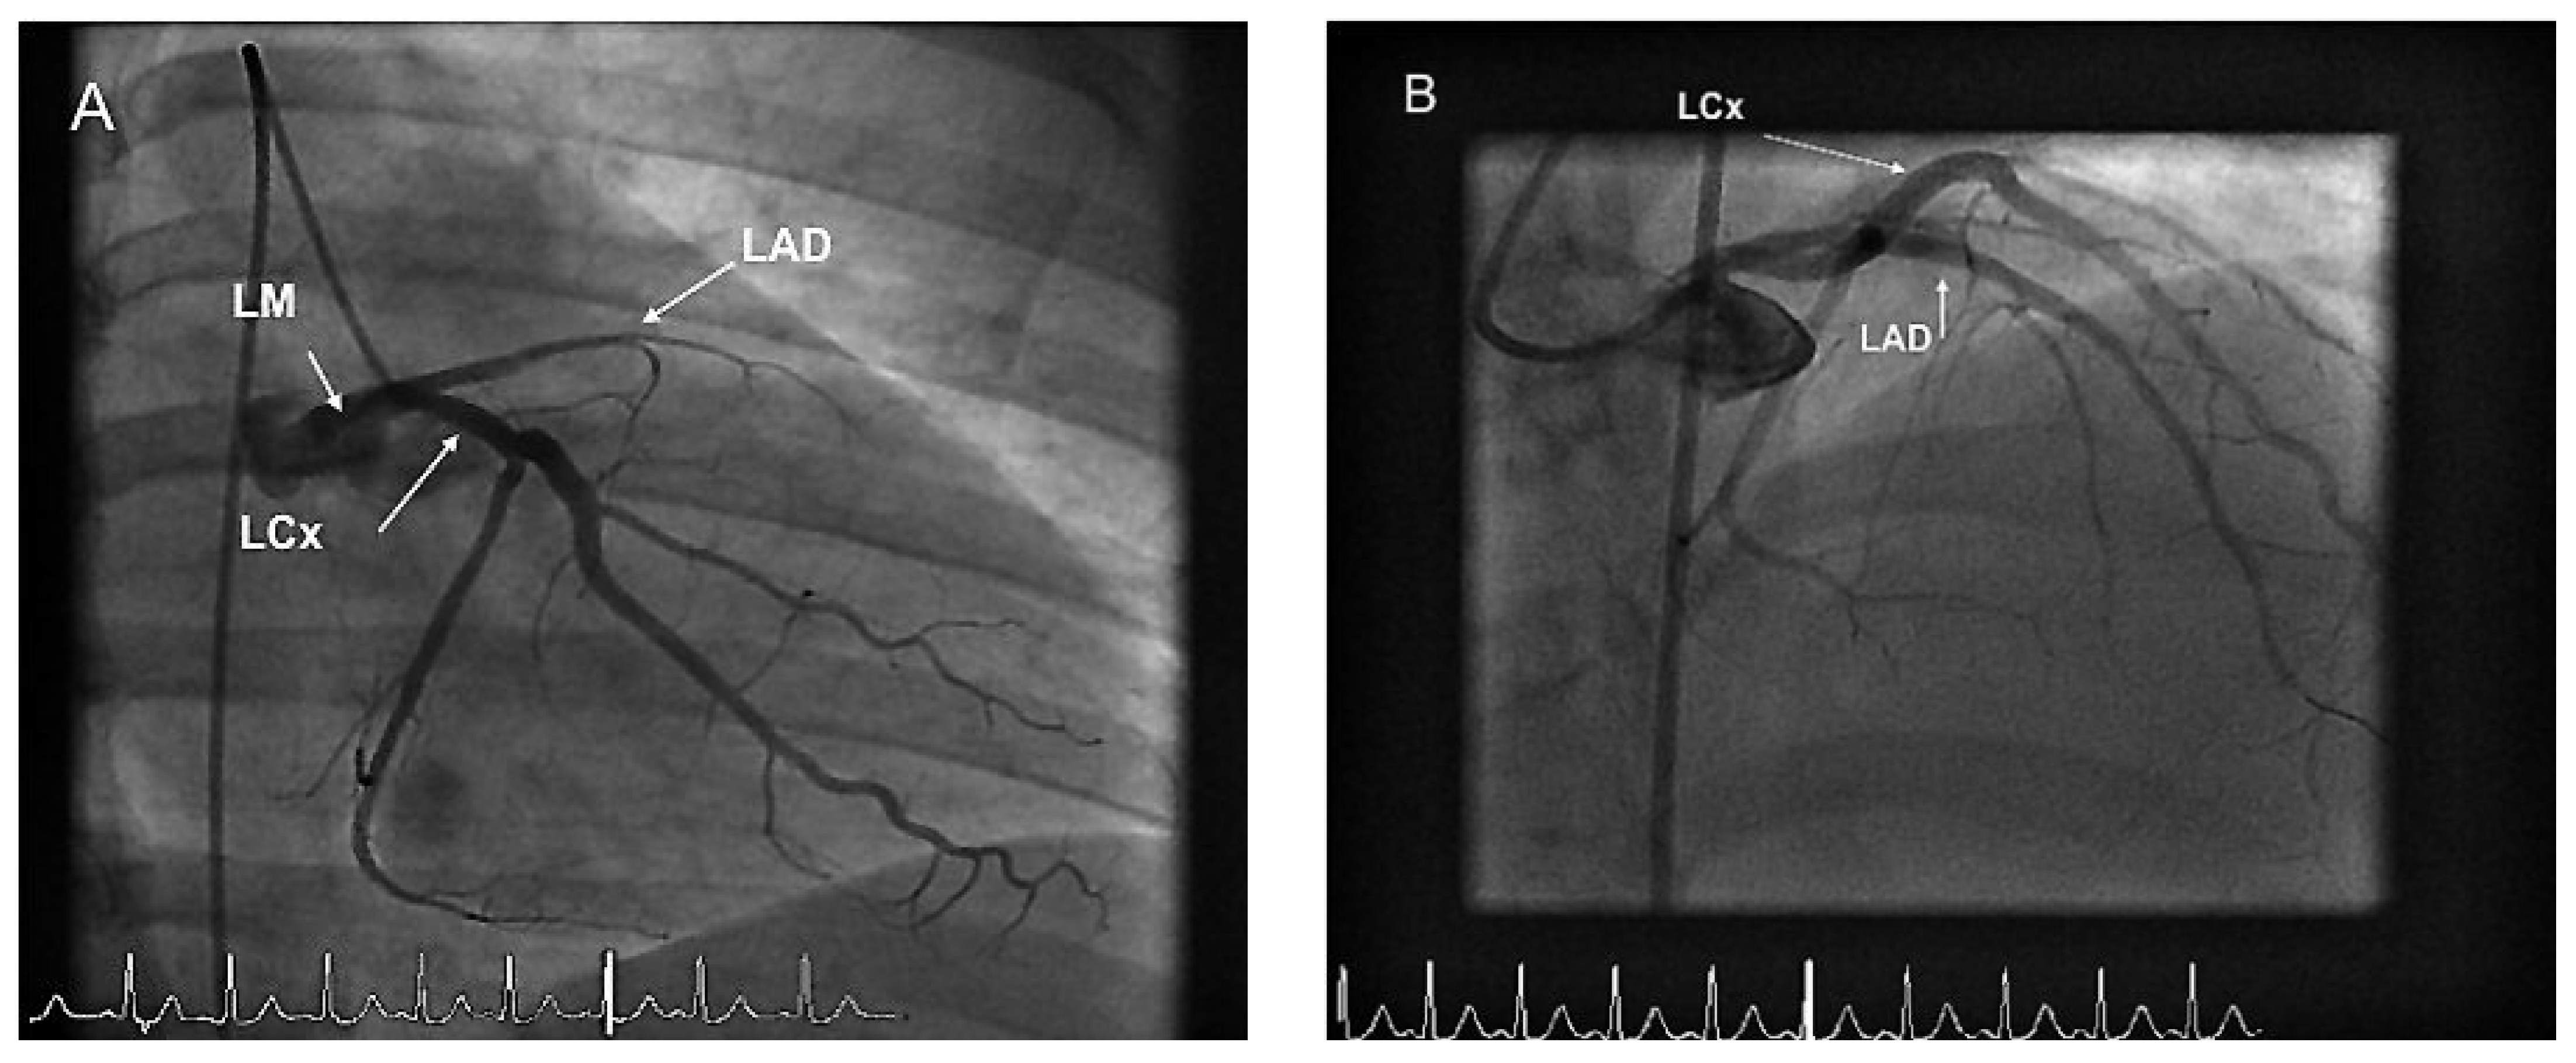

Case report